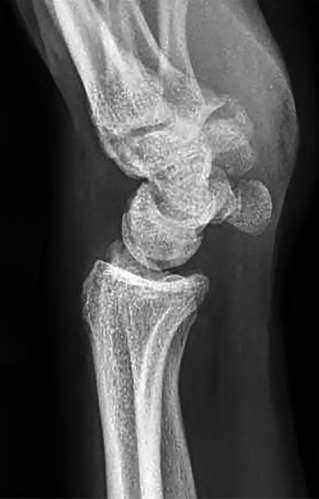

A 20-year-old park ranger trips and falls onto his right wrist with the wrist in extension and pronation. The local urgent care orders both radiographs and a CT, which you review and determine to be normal. The patient complains of ulnar-sided wrist pain. On exam, his tenderness is localized to the fovea. Ulnar deviation also causes him pain. There is no snapping sensation with wrist supination, flexion, and ulnar deviation. He otherwise has 5/5 strength to his first dorsal interosseous muscle with 4mm static two-point discrimination on the ulnar side of the 4th digit. Which of the following injuries is most likely responsible for his symptoms and exam?